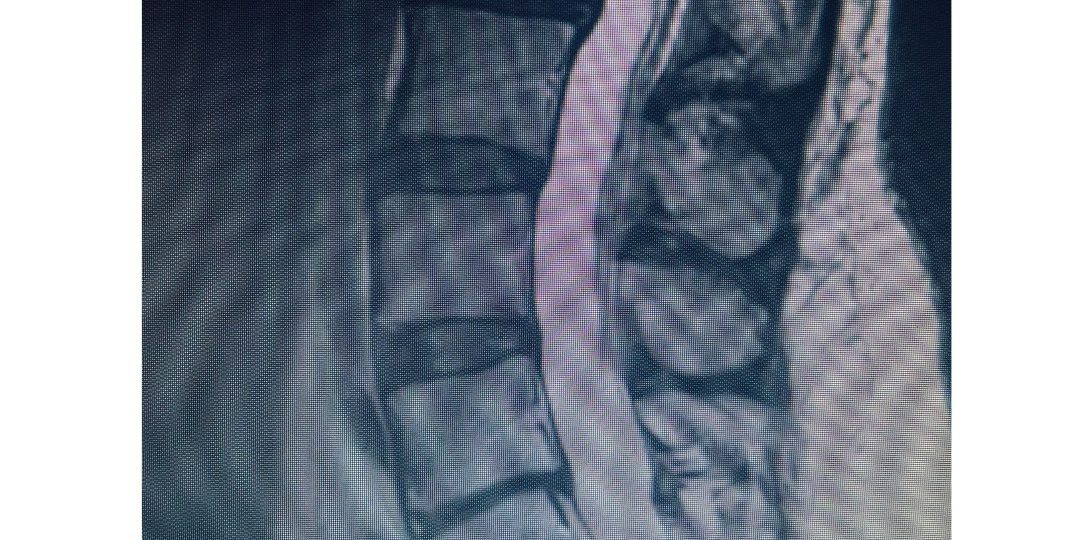

“This 53-year-old patient had a collapsed L5-S1 disc, retrolisthesis and foraminal stenosis contributing to severe low back pain. She had tried years of conservative (non-operative) treatment including physical therapy and injections without relief. At Texas NeuroSpine Surgery, we will always continue make every effort to treat your low back pain from a collapsed disc without surgery. However, surgery is appropriate for some carefully selected cases.

For this patient who had years of debilitating back pain, the solution was an ‘anterior-posterior’ or ‘front-back’ lumbar spine surgery (3rd photo). The surgery is also known as an ALIF (Anterior Lumbar Interbody Fusion) with posterior stabilization.